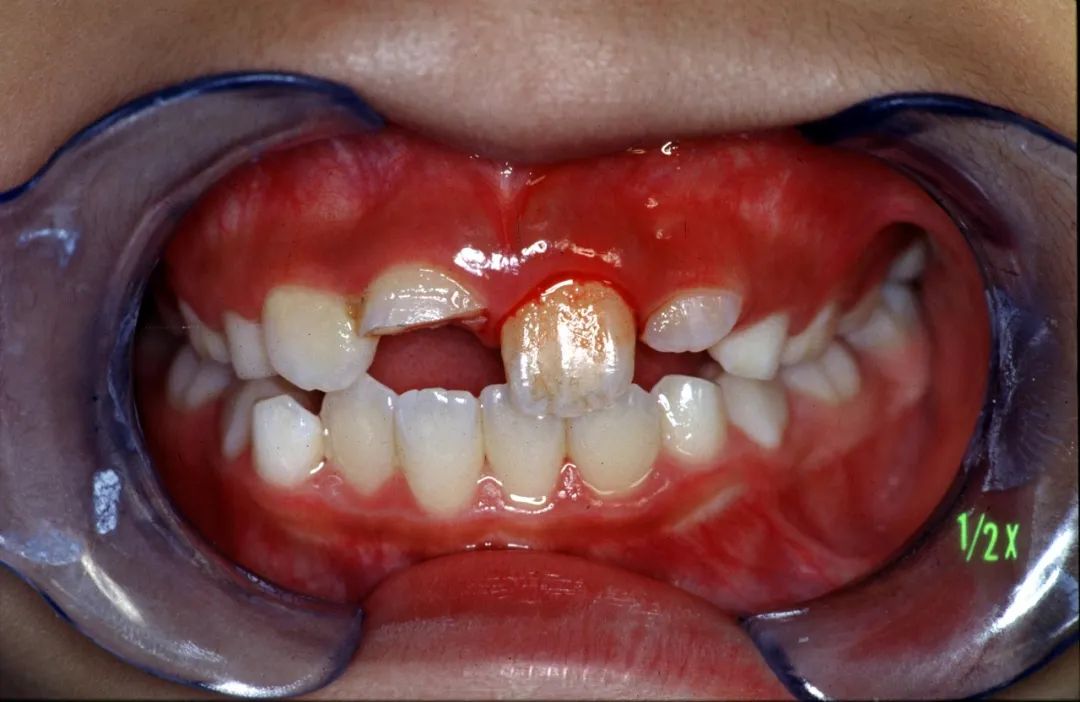

01|香港大学牙科全球领先,港人为何执着内地看牙